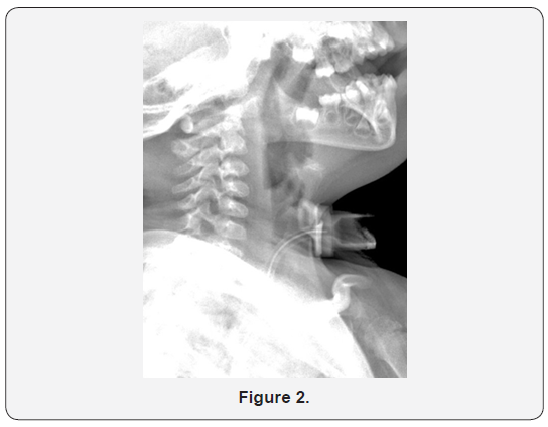

A 3 year old girl had a history of Down syndrome and bilateral choanal atresia with recurrent restenosis. She had undergone tracheostomy at age 3 months. She presented to the ENT emergency department in Sabah hospital with a history of t-tube separation from the flange during routine suctioning at home. When changing the t-tube, her mother noticed that the old tube was missing and immediately took her to our hospital. Prior to presentation, the patient had experienced a brief cyanotic attack. On presentation, she was distressed, with an oxygen saturation of 99% in room air. Her heart rate was 155 bpm, and her temperature was 36.10C. On auscultation, there were equal bilateral air entry and secretion sounds. Anterior, posterior, and lateral neck X-rays revealed a separated t-tube within the trachea (Figures 1 & 2). The patient was immediately taken to the operating room, and she underwent diagnostic fiber optic bronchoscopy. A portion of the t-tube was revealed within the trachea, near the carina. The dislodged t-tube, which had inner and outer diameters of 3 and 4.2 mm, respectively, was extracted from the left main bronchus with a rigid bronchoscope (size 3.7 mm) (Figure 3). Finally, the t-tube was changed. After recovery, the patient was transferred to the pediatric intensive care unit for close observation. A repeat chest X-ray revealed normal findings. The next day, she was transferred to the general ward and was doing well. Her vital signs were normal, and oxygen saturation was found to be 98% in room air.